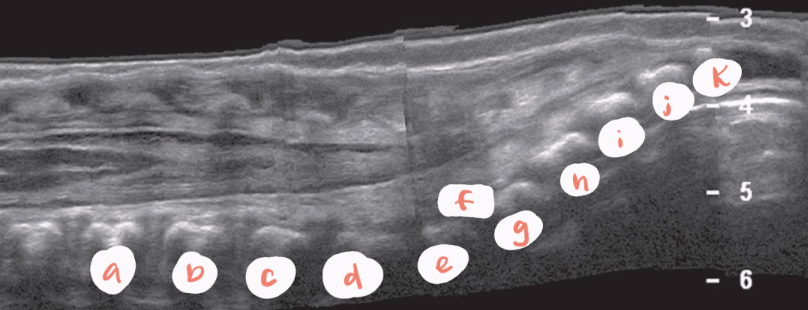

a

central canal of spinal cord

b

hypoechoic spinal cord

c

conus medullaris

d

pedicles/vertebral arches

f

nerve roots

g

coccygeal segments

h

T12

i

L1

e

filum terminale

J

L5

k

S1

arrow

LSJ